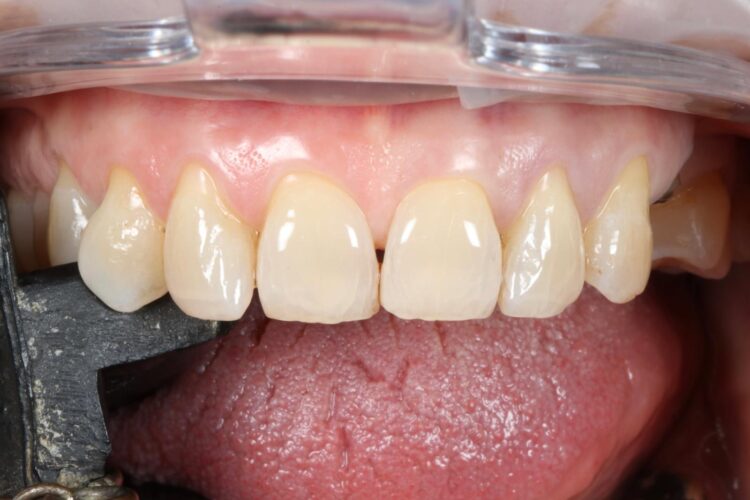

The implant in the UL5 was uncovered 3 months later to reveal healthy tissues. Three weeks later the final scan was taken (using trios intra-oral scanner) for the fabrication of the definitive crowns. On the day of crown fits both abutments were removed and the crowns seated. Due to the UL4 site having a custom healing abutment, which had been supporting our ideal emergence profile, it was much easier to engage this restoration and seat within the already moulded soft tissues.

With regards to the UL5 there was some blanching around the buccal aspect of the crown due to the use of a generic abutment, which does not offer any resemblance to the ideal emergence profile for the final restoration. Regardless good prosthetic positioning had been achieved to allow for screw-retained restorations in both implants. The final restorations were fitted as single unit layered zirconia crowns on titanium bases. The patient was delighted with the results.

Upon reflection of this case, a custom healing abutment may have delivered better soft tissue contouring than the generic abutment on the UL5. Healing may have taken longer, but it would have been easily tolerated by the patient and may have resulted in a better biological result with optimised aesthetics.